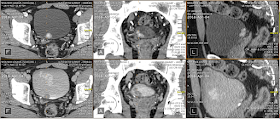

- April 4, 2018: CT Scan - "Lobulated hypervascular mass arising from the posterior surface of the bladder on the right measuring 25 X 15 X 12mm"